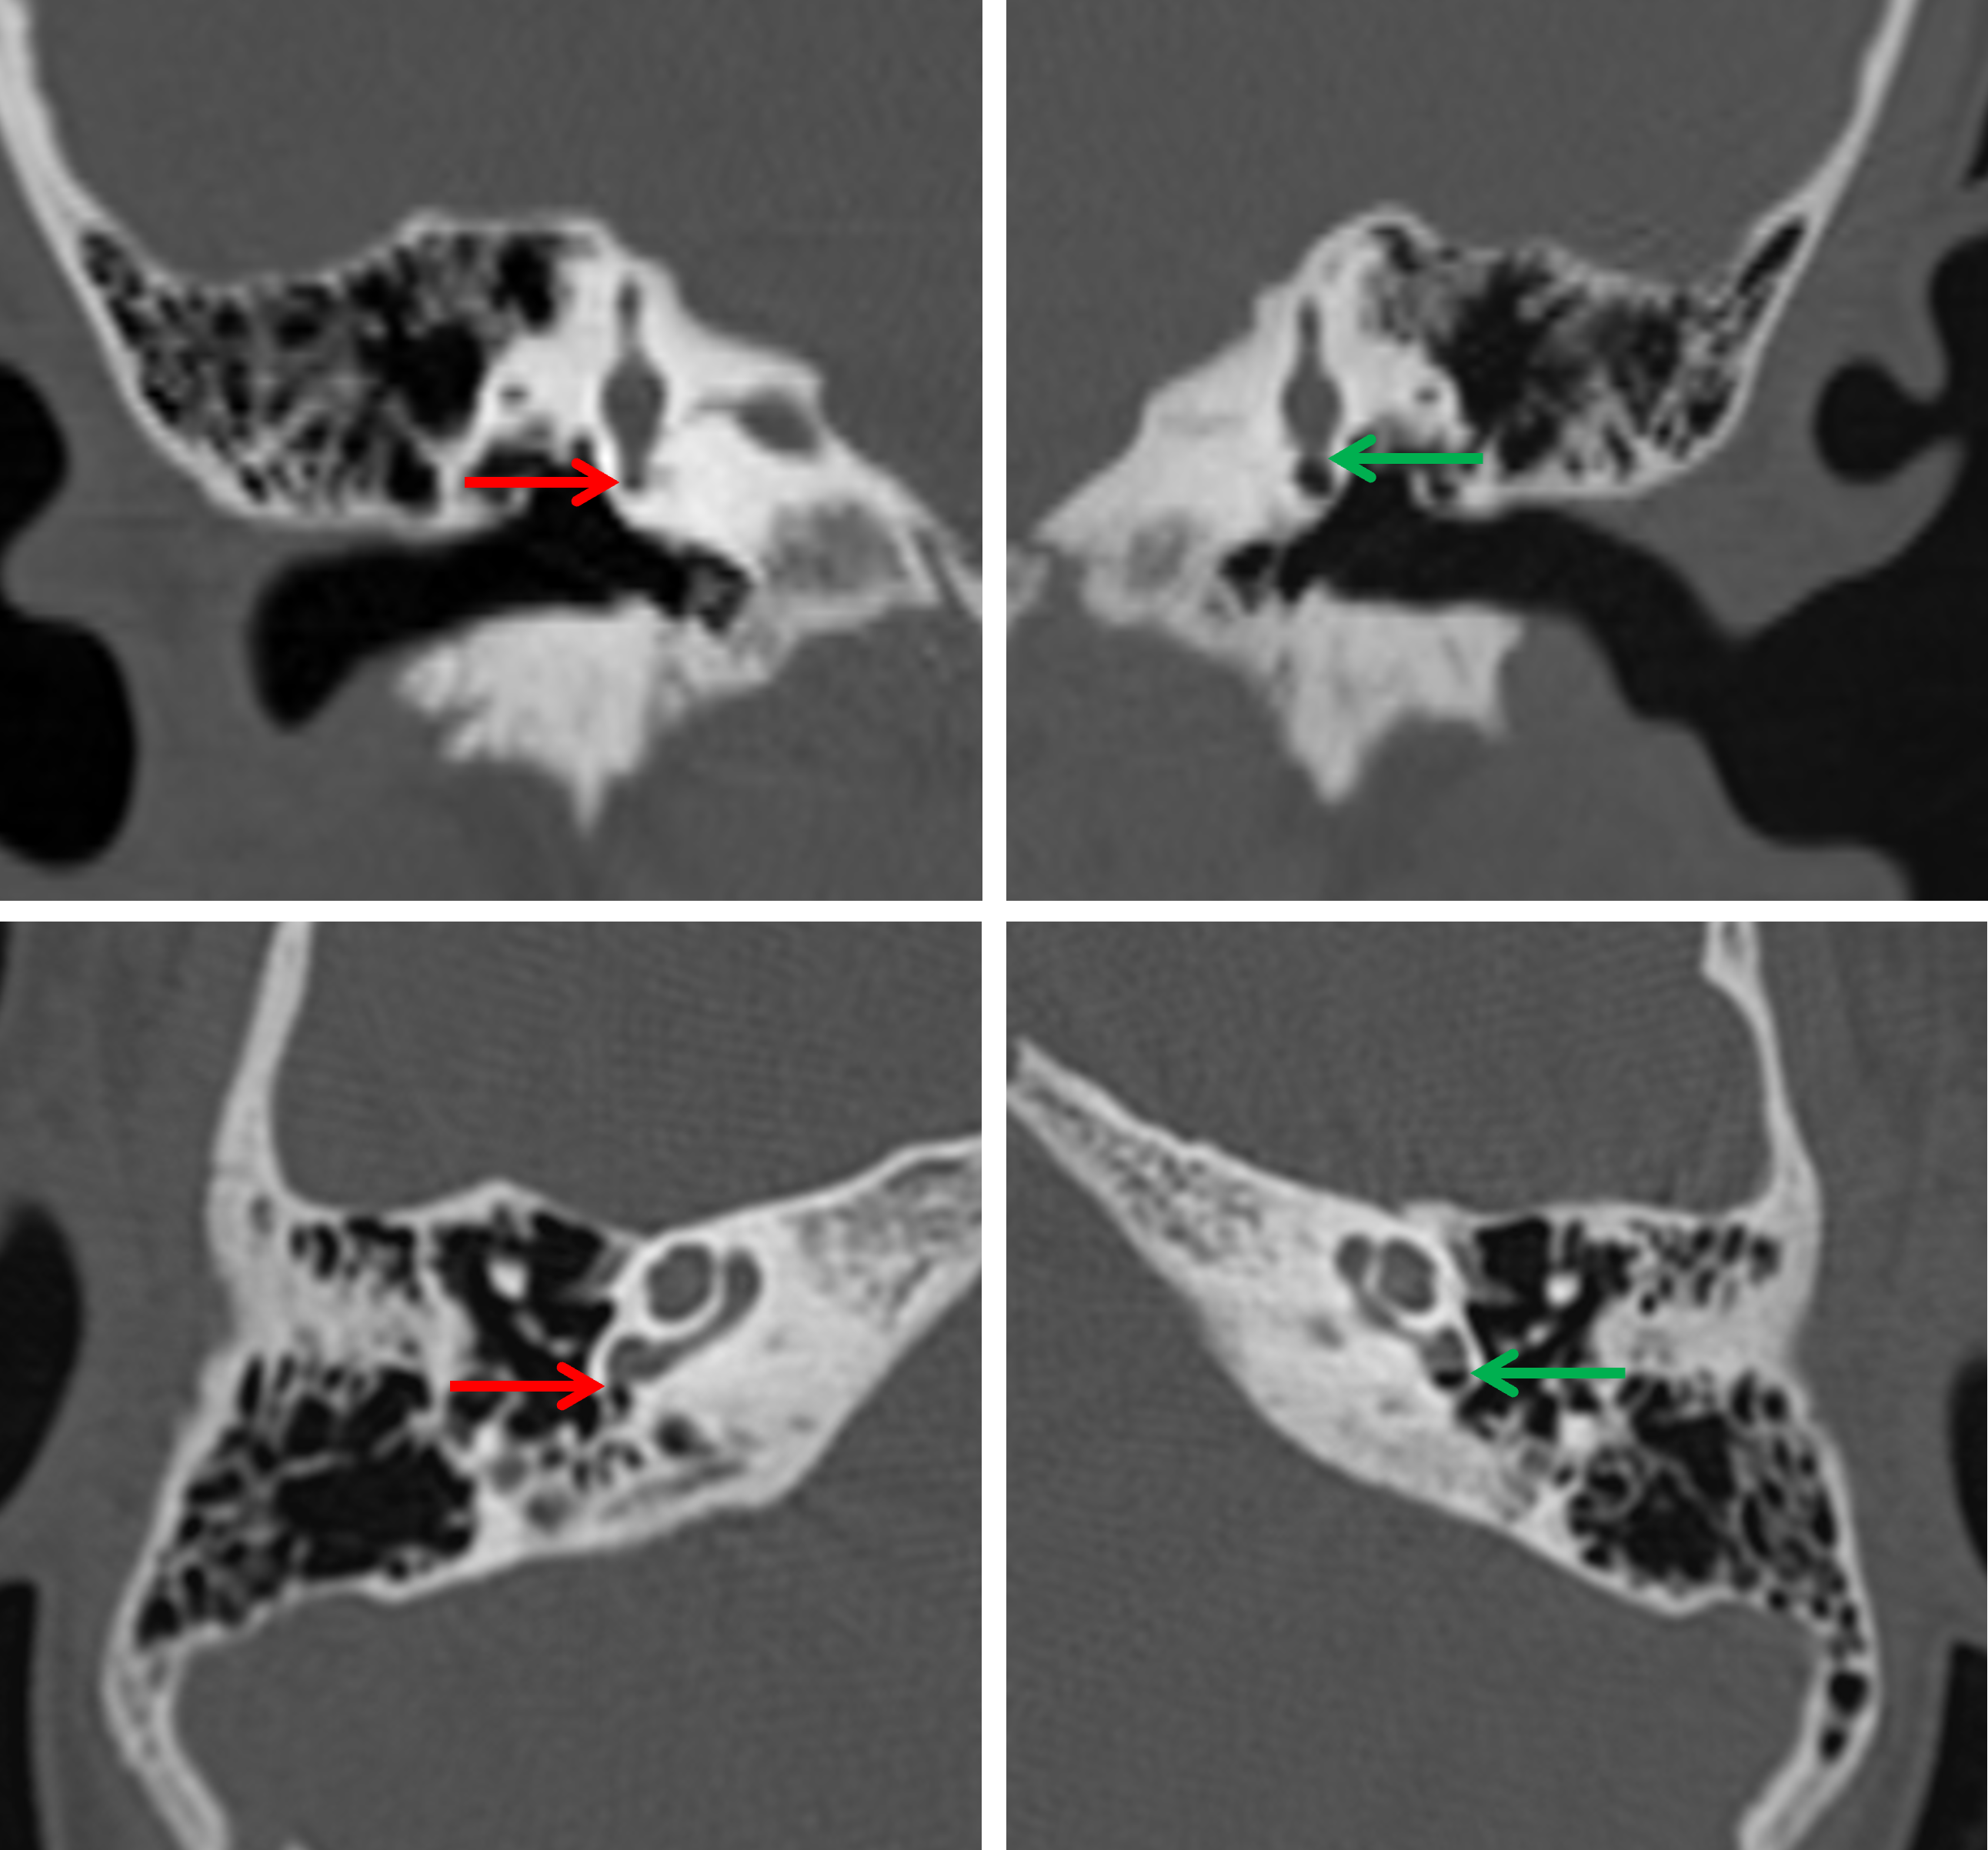

Age: 6

Sex: Male

Indication: Right-sided conductive hearing loss

Round window stenosis